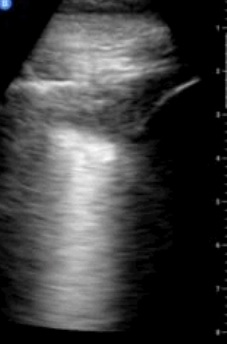

• Ecografía pulmonar: 3 consolidaciones en cara posterior de hemitórax derecho (PD4-PD6), una de ellas triangular en base derecha periférica, sin broncograma, sugerente de infarto pulmonar. El resto oligonales sin broncograma.